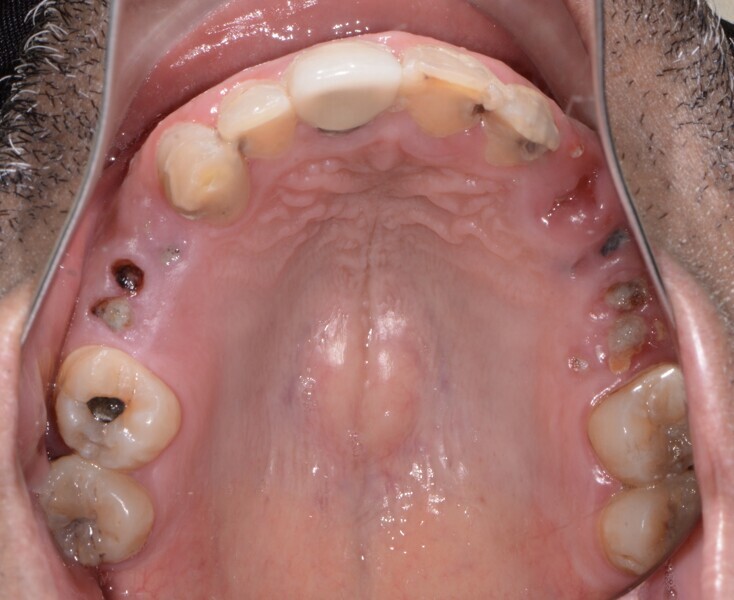

Fig. 2: Pre-op maxillary occlusal view.